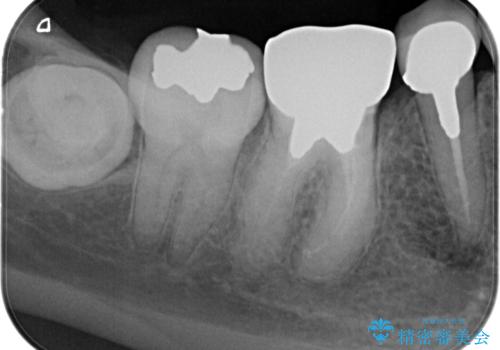

【外部吸収】根管治療、外科治療からのオールセラミッククラウン

- 歯肉の腫脹と被せ物の不適合を主訴に来院されました。

根管治療後、外部吸収を認めたため歯周外科を行ない歯冠修復を行なっております。